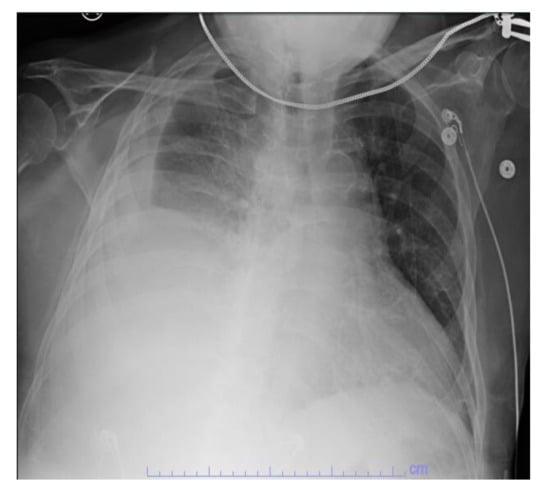

Initial laboratory studies showed elevated white blood cells (WBC) 22.6 × 109/L with neutrophilia, bicarbonate 21 mmol/L, lactic acid 6.5 mmol/L, anion gap 17, ALT 71 IU/L, AST 69 IU/L, and ALP 450 IU/L. ECG showed atrial fibrillation with a rapid ventricular response. CXR showed acute right pleural effusion (Figure 1). The patient was intubated for respiratory failure. He was also started on antibiotics (piperacillin-tazobactam and azithromycin) and intravenous normal saline with no improvement in blood pressure. The patient was then started on intravenous vasopressor support with norepinephrine and vasopressin and admitted to the intensive care unit (ICU).

Figure 1. CXR showing acute right pleural effusion.